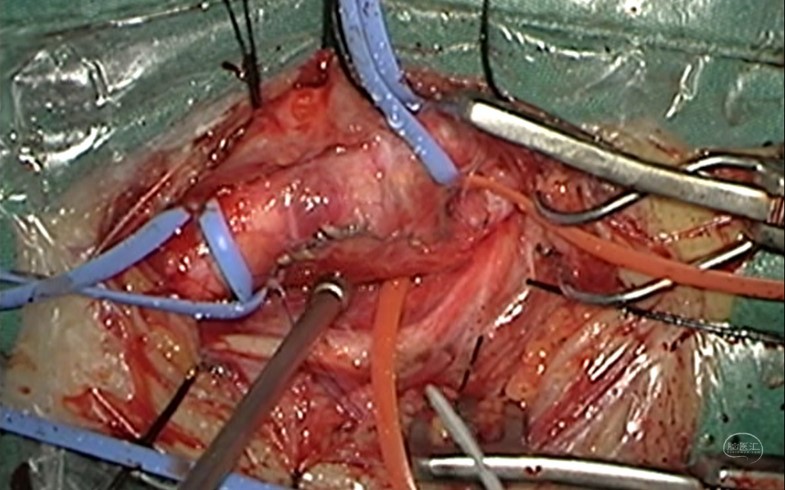

颈动脉内膜剥脱术